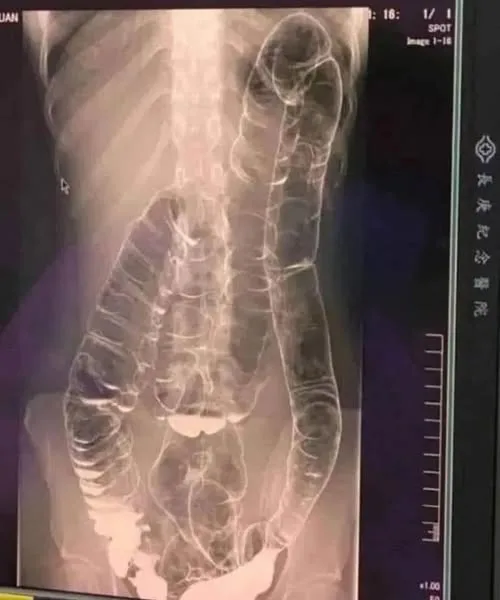

Questa è una radiografia di una giovane donna che soffre di stitichezza cronica. Dopo aver accusato sintomi persistenti per oltre due settimane, ha consultato un medico e ha ricevuto i risultati della radiografia qui sotto… Chi non ha mai sofferto di stitichezza? Questo problema, spesso percepito come banale, può trasformarsi in un vero e proprio … Read more